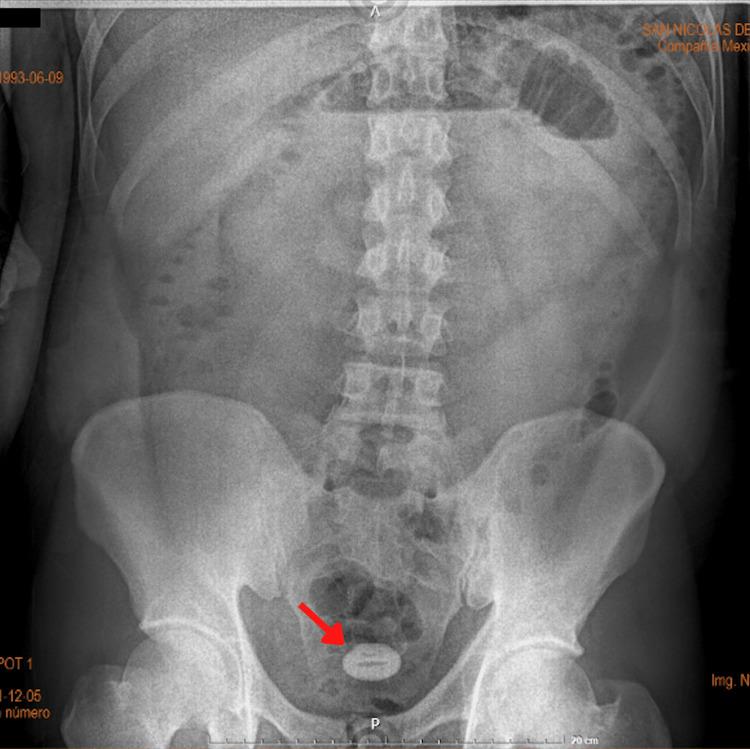

Gallstone ileus is a rare presentation of gallbladder disease. It is mostly encountered in female and elderly patients. It occurs when a stone causes a fistula between the gallbladder and the intestinal lumen. More than half of the patients do not have a history of biliary disease. Surgical intervention is still considered the best treatment option; however, the best choice between one-stage and two-stage surgery is still unknown. We present a gallstone Ileus case in a patient with uncommon epidemiological characteristics: a 28-year-old male Hispanic patient without a gallbladder disease history.

胆结石性肠梗阻是胆囊疾病的一种罕见表现。多见于女性和老年患者。当结石导致胆囊与肠腔之间形成瘘管时就会发生。超过半数的患者没有胆道疾病史。手术干预仍然被认为是最佳治疗选择;然而,一期手术和二期手术之间的最佳选择仍不明确。我们报告一例具有不寻常流行病学特征的胆结石性肠梗阻病例:一名28岁无胆囊疾病史的西班牙裔男性患者。